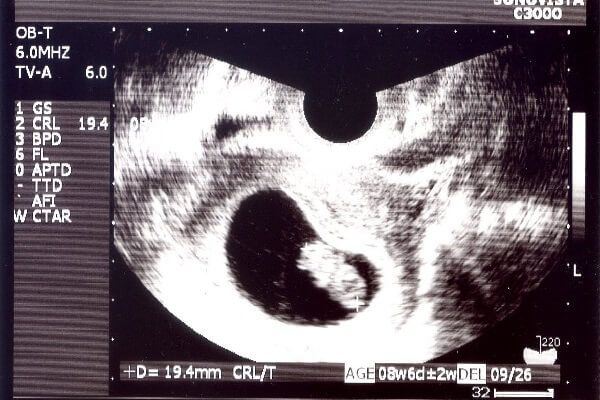

妊娠8週目になるとついに妊娠3ヶ月に入ります。もうほとんどの人が病院で受診し、超音波で赤ちゃんを確認できる頃ですね。妊娠8週目の赤ちゃんはどのような成長をみせてくれるのでしょうか。

妊娠8週目になると赤ちゃんは胎芽から胎児と呼ばれるようになります。(妊娠10週からという説もあります。)ほとんどの赤ちゃんが心拍の確認ができ、母子手帳をもらうママが多い時期ですね。

大きさは13~18ミリほどまで成長しているでしょう。まだ胎盤は完成していませんが、へその緒を通してママから少しずつ栄養をもらうようになっていきます。